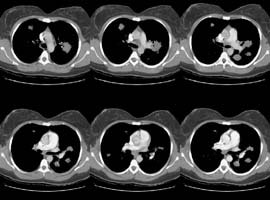

A CT scan of the chest was performed and selected HRCT images were also

obtained: